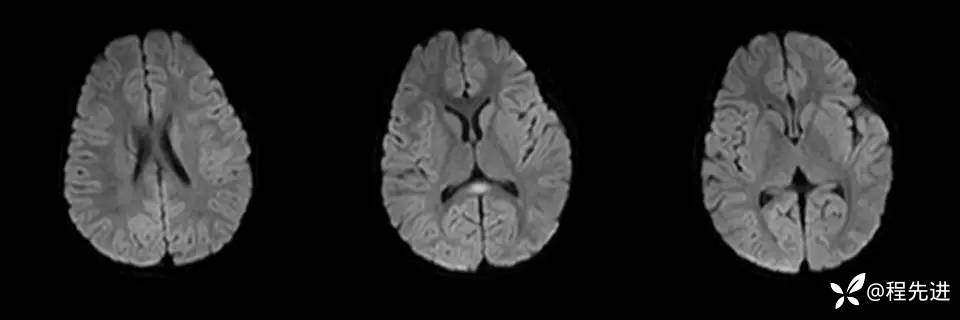

患者性别:女

患者年龄:3岁

主诉:间断呕吐2天,伴腹泻1天,惊厥1次

现病史:2天前进食后呕吐,非喷射状,1天前出现腹泻,每日4-5次。入院2小时前出现抽搐发作

辅助检查:便常规轮状病毒(+)

伴可逆性胼胝体压部病变的轻度脑炎 (7)